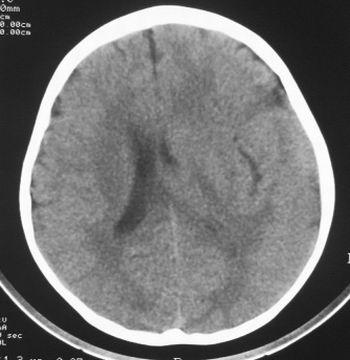

患儿,男,8岁,外伤2小时,无恶心、呕吐,四肢活动正常。既往无任何不适,智力发育正常。

典型的左中颅窝蛛网膜囊肿。

典型的左中颅窝蛛网膜囊肿。最常见的发病部位,张力比较高,相应颅板受压变薄。赶紧治疗,脑组织的功能可能部分恢复。